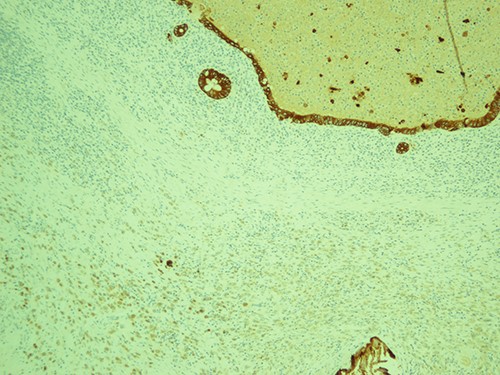

The most represented population is pancytokeratin negative, confirming its non-epitheliod and non-neoplastic nature; pancytokeratin, magnification ×10.